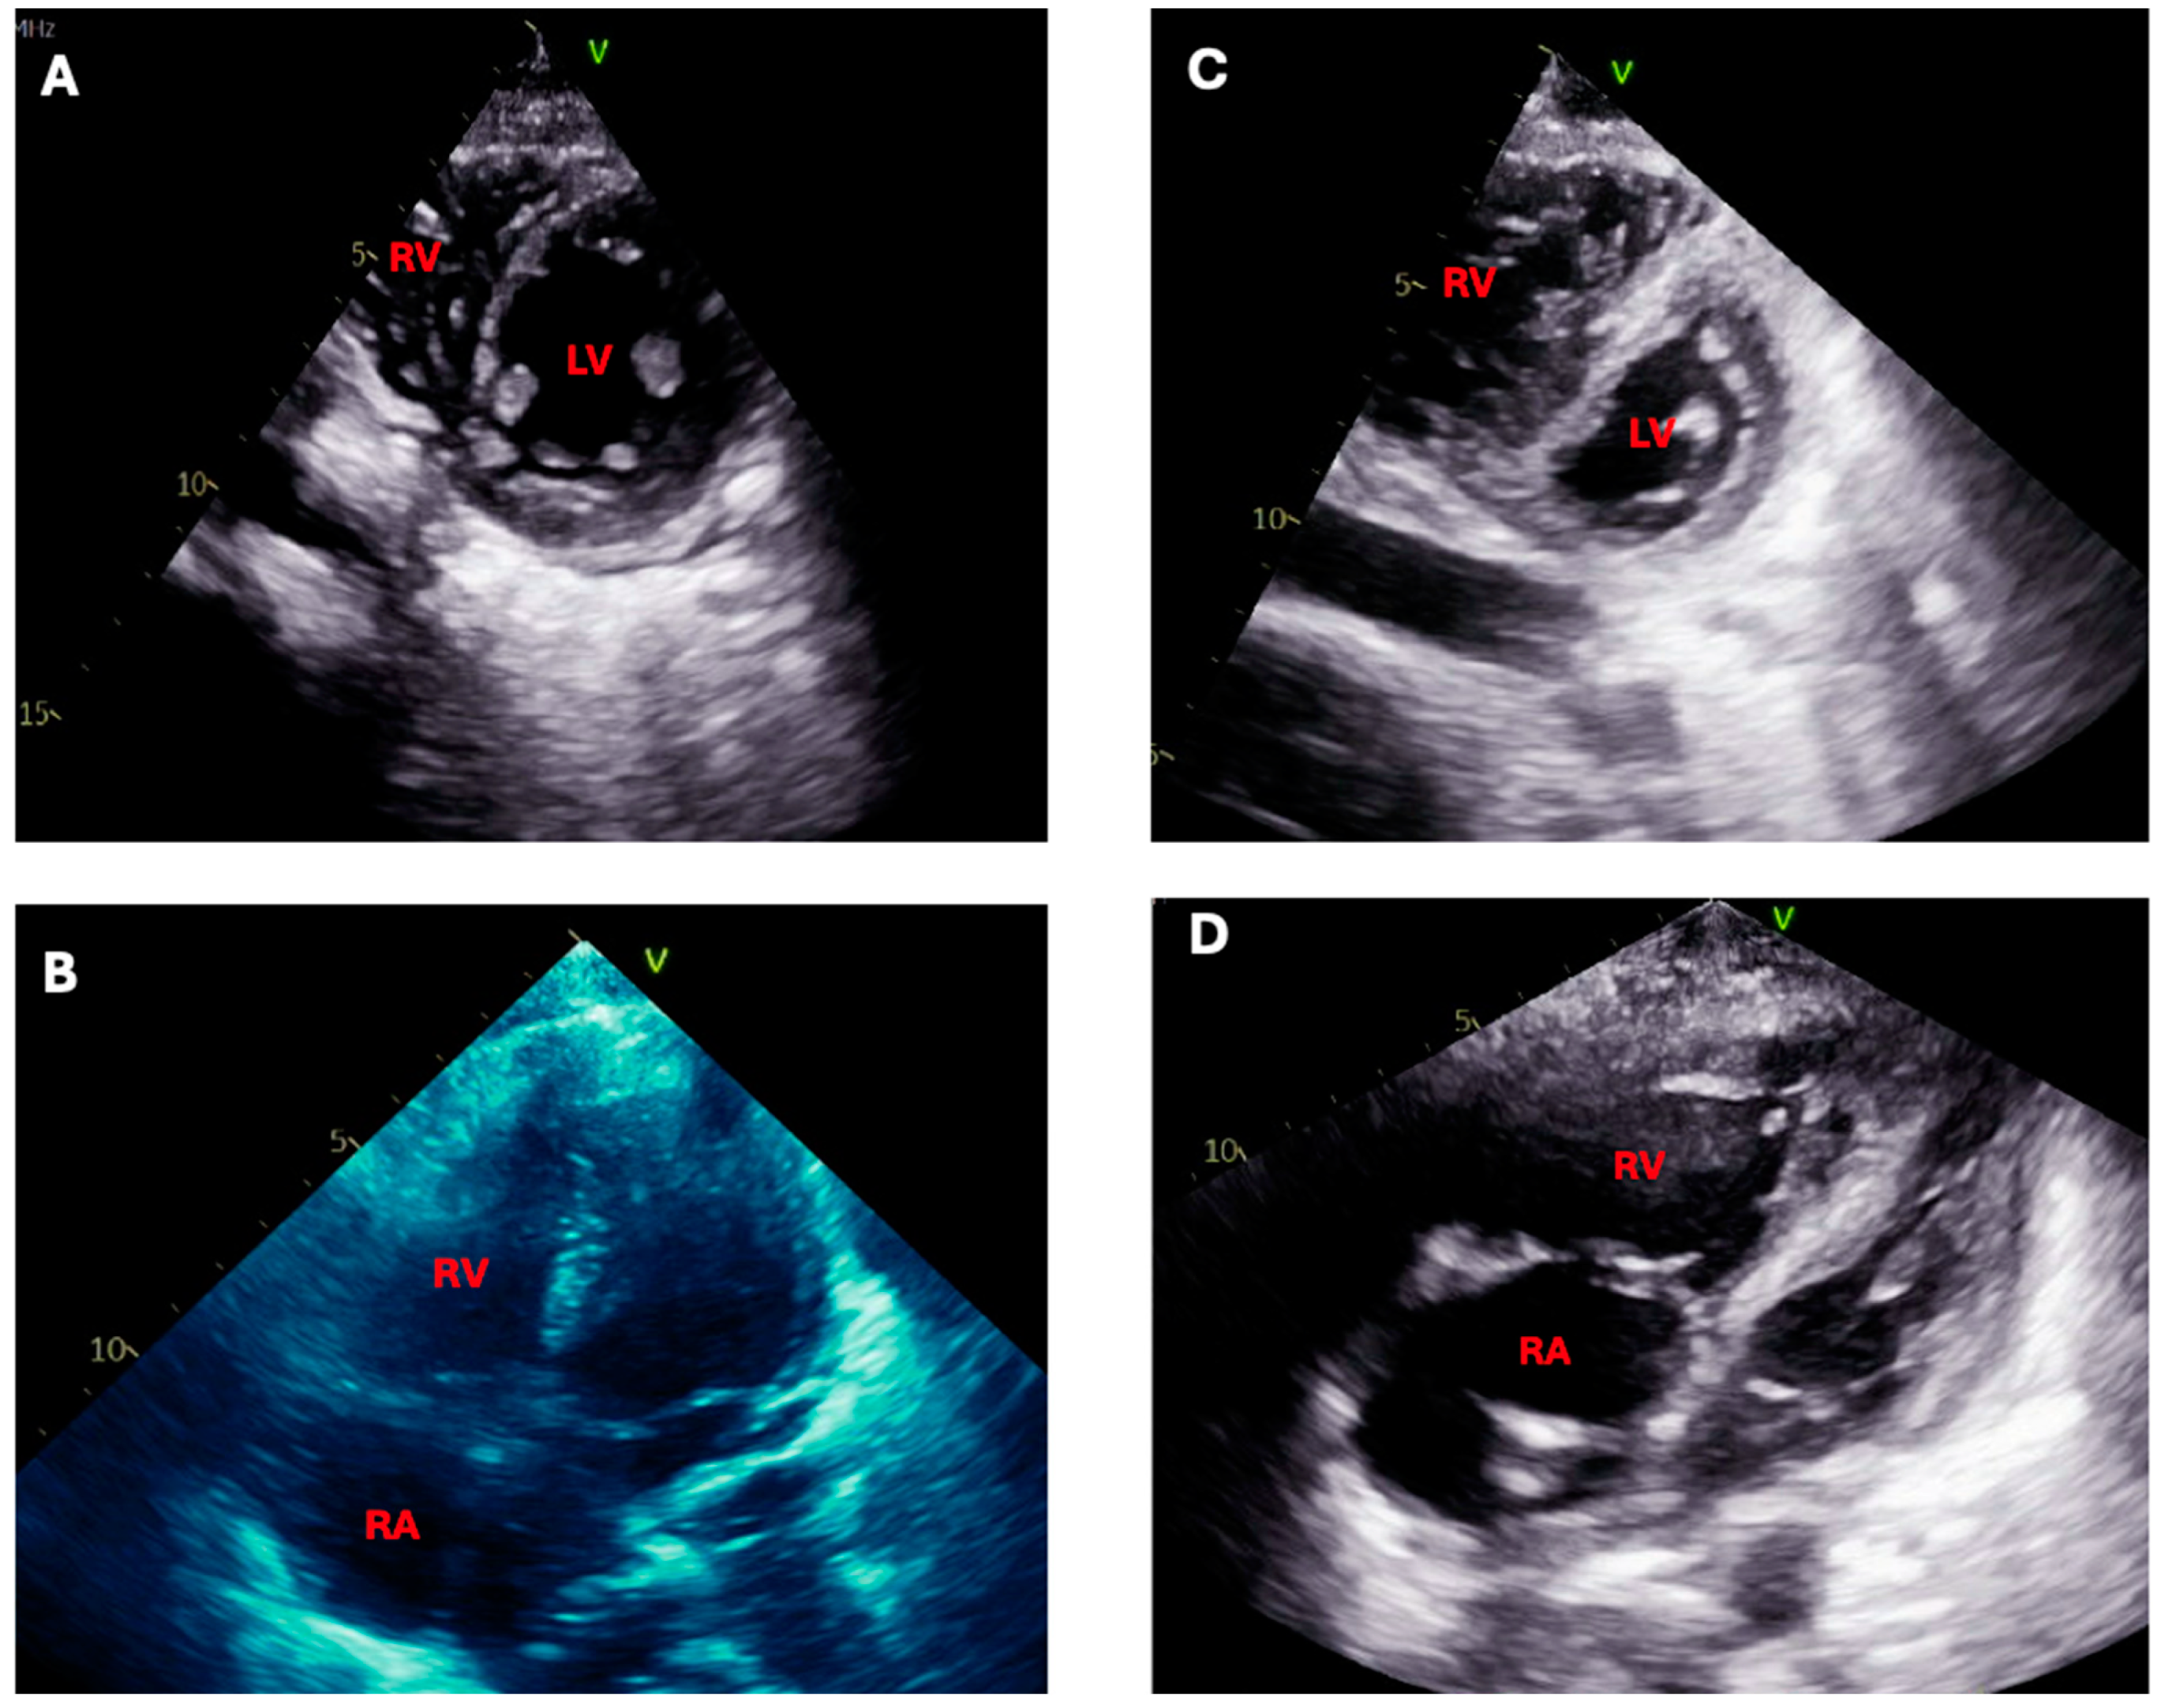

4.4. Management of Concomitant Pulmonary Hypertension

- Arrigo, M.; Price, S.; Harjola, V.-P.; Huber, L.C.; Schaubroeck, H.A.I.; Vieillard-Baron, A.; Mebazaa, A.; Masip, J. Diagnosis and treatment of right ventricular failure secondary to acutely increased right ventricular afterload (acute cor pulmonale): A clinical consensus statement of the Association for Acute CardioVascular Care of the European Society of Cardiology. Eur. Heart J. Acute Cardiovasc. Care 2024, 13, 304–312. [Google Scholar] [CrossRef]

- Behr, J.; Ryu, J.H. Pulmonary hypertension in interstitial lung disease. Eur. Respir. J. 2008, 31, 1357–1367. [Google Scholar] [CrossRef]

- Nathan, S.D.; Hassoun, P.M. Pulmonary Hypertension due to Lung Disease and/or Hypoxia. Clin. Chest Med. 2013, 34, 695–705. [Google Scholar] [CrossRef]

- Caminati, A.; Cassandro, R.; Harari, S. Pulmonary hypertension in chronic interstitial lung diseases. Eur. Respir. Rev. 2013, 22, 292–301. [Google Scholar] [CrossRef]